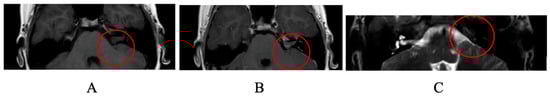

A Case Report of Malignant Cerebellopontine Angle Lesion Highlighting the Interdisciplinary Diagnostic Challenge in the Case of Unilateral Progressive Hearing Loss

1. Case Report